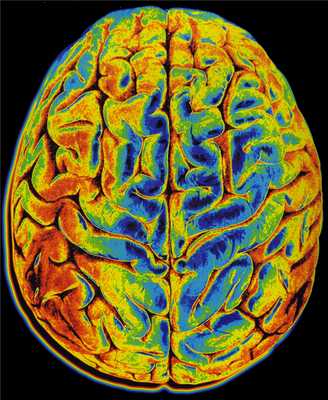

МРТ головного мозга. Т2-взвешенная аксиальная томограмма. Арахноидальная киста. Цветовая обработка изображения.

МРТ головного мозга. Т2-взвешенная аксиальная МРТ. Цветовая обработка изображения.